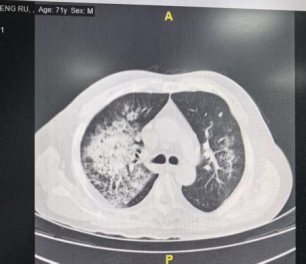

经过11月10日到11月16日1周抗感染治疗患者病情好转,吸氧浓度下调,氧合指数改善,后转回消化内科继续保肝治疗。

胸部CT变化:

11月19日: